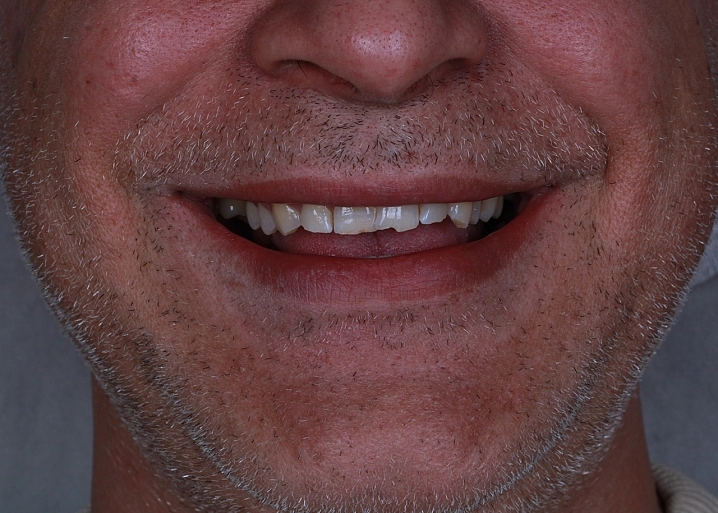

Циркониевый мостовидный протез представляет собой постоянную конструкцию, которая фиксируется на несколько опорных имплантов. Протез устанавливается после периода остеоинтеграции имплантатов через 3-6 месяцев. Коронки соединены между собой каркасом и представляют единое целое.

Существует 2 вида реставраций: с нанесением керамической массой и методом раскрашивания. Второй вариант в нашей клинике применяется чаще всего. Этот метод дает высокий эстетический результат. Первый вариант с нанесением керамики имеет недостаток, керамика может со временем скалываться, что вызывает неудобство в использовании протеза.